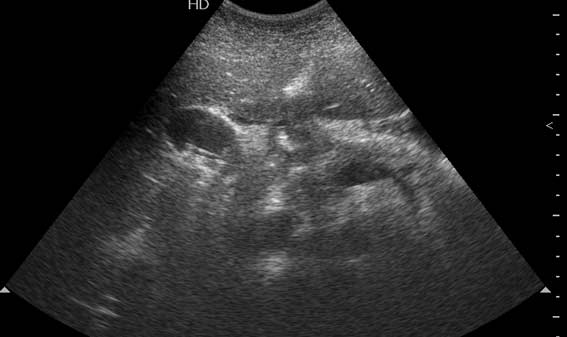

Мужчина 37 лет. Поступил в приемое отделение БСМП. Болен уже неделю, лечился в поликлинике. Сегодня боли усилились и стали нестерпимыми.

2 Между ж.пузырем и головкой панкреас -полый орган с отечными стенками-12 п.к.?(может быть сочетание язв.б-ни и ж.кам.б-ни)Если камень не в устье,то показана ФГС

Вы правильно разглядели пенетрирующую язву 12ПК. Перфорация прикрыта тканью печени, есть чуть-чуть свободной жидкости в ложе желчного пузыря. А ведь можно было "диагностировать" и острый холецистит!